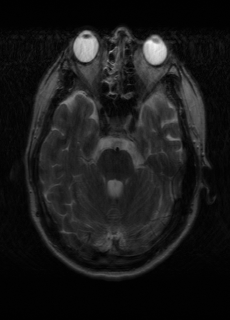

λT1=6.63subscript𝜆subscript𝑇16.63\lambda_{T_{1}}=6.63 Refer to caption (a) 35.46/0.9431 Refer to caption (b) 40.82/0.9826 Refer to caption (c) 41.84/0.9857 Refer to caption (d) 42.12/0.9867 Refer to caption (e) PSNR/SSIM

λT2=2.11subscript𝜆subscript𝑇22.11\lambda_{T_{2}}=2.11 Refer to caption (f) 32.34/0.9254 Refer to caption (g) 36.19/0.9699 Refer to caption (h) 36.42/0.9711 Refer to caption (i) 36.78/0.9695 Refer to caption (j) PSNR/SSIM

λflair=8.00subscript𝜆𝑓𝑙𝑎𝑖𝑟8.00\lambda_{flair}=8.00 Refer to caption (k) 42.54/0.9489 Refer to caption (l) 45.24/0.9837 Refer to caption (m) 45.89/0.9868 Refer to caption (n) 46.35/0.9880 Refer to caption (o) PSNR/SSIM

Figure 4: Visual comparison of different recovery methods on real data